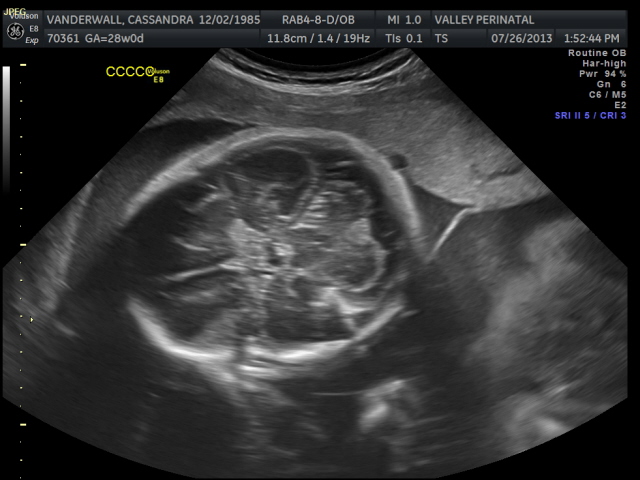

The weight of each baby is estimated based on the length of the baby’s humerus (bone in upper arm) and femur (bone in upper leg), the circumference of their abdomen and their head circumference.

All of their organs (kidneys, bladders, hearts, brains, stomachs) look great and are also appropriate sizes. The blood flow to Elle has improved and has stabilized. All heart rates remain within normal limits, and are often on the higher side, which is probably because they just can’t sit still. We are truly excited to meet our little wiggle worms!